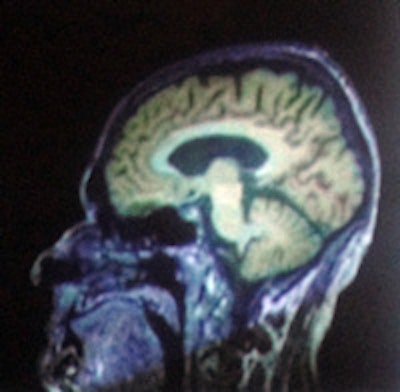

Rappresentazione di tumore cerebrale realizzata mediante fusione fra una immagine MP-RAGE T1-pesata ed una immagine PET con F-fluoro etil-tirosina (FET). Per le immagini i ringraziamenti vanno a N. Jon Shah, PhD.

Nello studio di una neoplasia cerebrale, la scansione ibrida con F-fluoro etil-tirosina e RM a campo ultra-elevato consente non solo di delineare con precisione la lesione, ma mostra il coinvolgimento delle regioni cerebrali circostanti, ha affermato Shah.